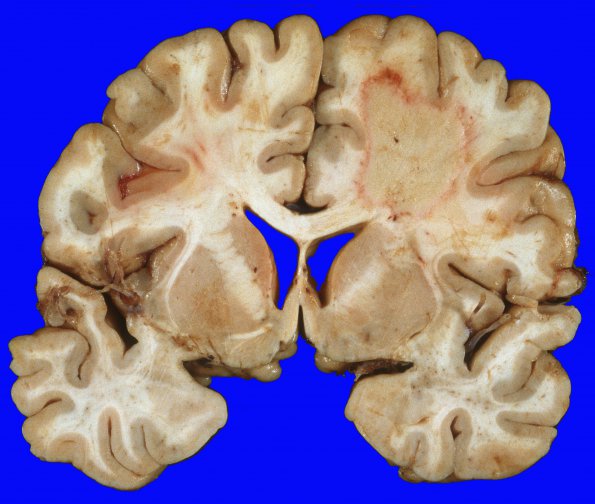

13A1,2 At autopsy the brain consisted of symmetrical cerebral hemispheres and there was no evidence of leptomeningeal infiltration by lymphoma. Coronal sections demonstrate a 7 x 5 x 5 cm well demarcated tumor mass in the right frontal lobe with a hyperemic rim and surrounding edema. The mass is located in the deep white matter and focally extends into the cortical grey matter.